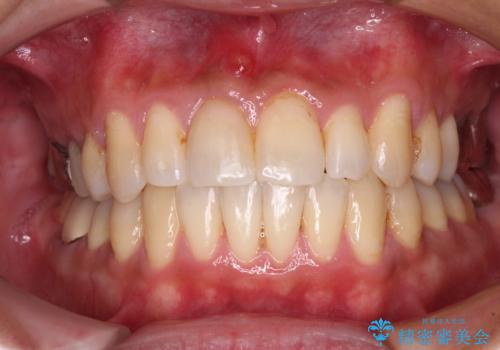

- 上下前歯のデコボコと下顎小臼歯の欠損によるスペースを気にして来院された患者様です。

欠損により下顎歯列は相対的に小さく、上顎に深く咬みこんでしまうディープバイトとなっていました。

インビザラインによる治療を希望されたため、左側のスペースは閉じ、右側はスペースをより拡大し、インプラント補綴を行うこととしました。

咬合力が強く、インビザラインのみではディープバイトを改善することができず、半年間ほどワイヤー装置による矯正治療を行いました。

インプラントの埋入は矯正治療中に行い、矯正治療後はインプラント上補綴および、前歯のセラミック治療を行いました。